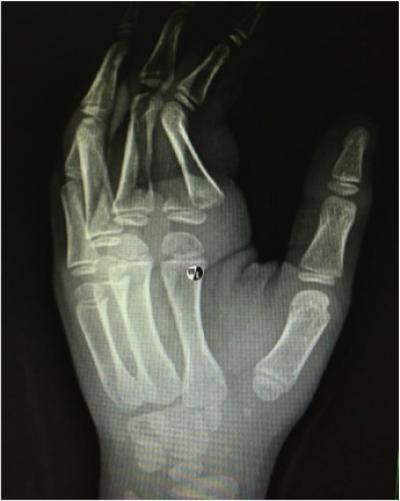

Figure 1: Radiograph of the left hand showing a displaced and angulated fracture of the base of the proximal phalanx of the left index finger (Salter Harris Type 2) (yellow arrow)